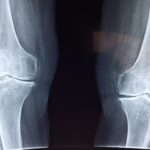

冬場は路面凍結や雪道による転倒リスクが高まります。骨粗鬆症を有する高齢者では、転倒による骨折がQOLの低下や寝たきりにつながる可能性があるため、特に注意が必要です。